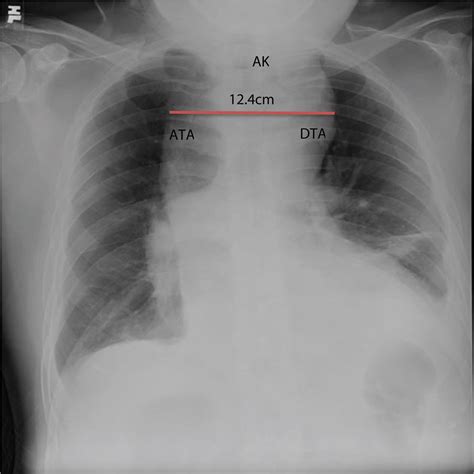

Diagnosing a Descending Aortic Aneurysm typically involves a combination of medical history, physical examination, and imaging tests. Common diagnostic methods include:

• Chest X-ray: This can reveal a widened aorta.